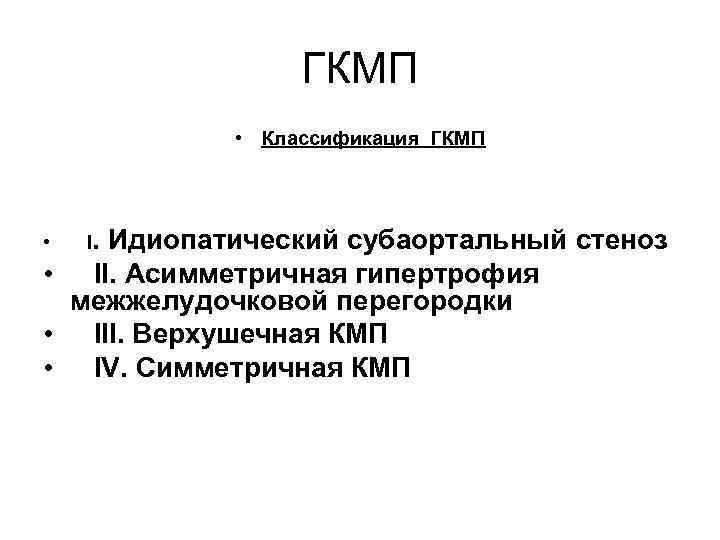

ГКМП • Классификация ГКМП Идиопатический субаортальный стеноз • II. Асимметричная гипертрофия межжелудочковой перегородки • III. Верхушечная КМП • IV. Симметричная КМП • I.

ГКМП • Классификация ГКМП Идиопатический субаортальный стеноз • II. Асимметричная гипертрофия межжелудочковой перегородки • III. Верхушечная КМП • IV. Симметричная КМП • I.